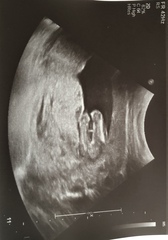

Had my 16 week scan today and found out we’re having a girl! Feels so much more real and exciting now! Baby was moving tons, it’s so freaky seeing her move so much and not being able to feel it yet. Attached photo of our little creepy alien and the gender reveal shot.